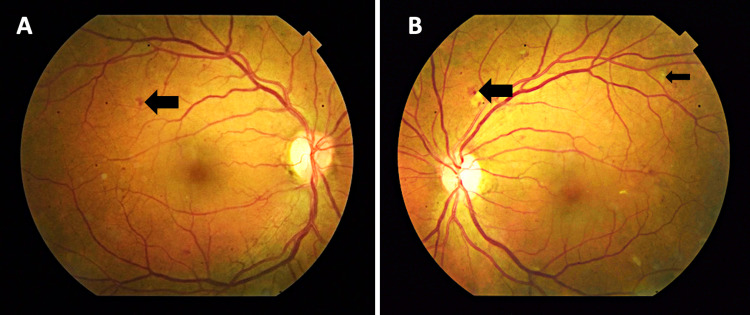

On examination, her visual acuity (VA) with her habitual glasses was 20/60 in the right eye (OD) and 20/70 in the left eye (OS), pin holed to 20/40 OD and 20/40 OS. The pupils were round and reactive to light OU, with no relative afferent pupillary defect. External examination, extraocular muscle movements, and counting finger visual field tests were normal. Her intraocular pressure was 16 mmHg in the right eye and 17 mmHg in the left eye, measured with a tonopen. The dilated fundus examination revealed rare cotton wool spots, microaneurysm, dot-blot hemorrhages, and vascular attenuation consistent with moderate, non-proliferative diabetic retinopathy in both eyes without any signs of macular edema (Figure 1). Her optic cups appeared normal with no signs of glaucoma. Given her decrease in vision and clinical presentation of non-proliferative diabetic maculopathy, we decided to run a macular optical coherence tomography (OCT) scan (Figure 2). The fovea showed a normal contour, no central macular edema, and an average central retinal thickness of 275 µM OD and 273 µM OS.